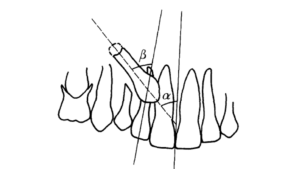

Determinação dos ângulos a e b do posicionamento dos caninos impactados

A outra avaliação envolve o ângulo formado pela linha média e o longo-eixo do canino em erupção (α) e o ângulo formado entre os longos-eixos do canino e incisivo lateral (β). Valores superiores a 25o para o ângulo α e 28o para o β, aumentam a probabilidade de reabsorção do incisivo em 50%.